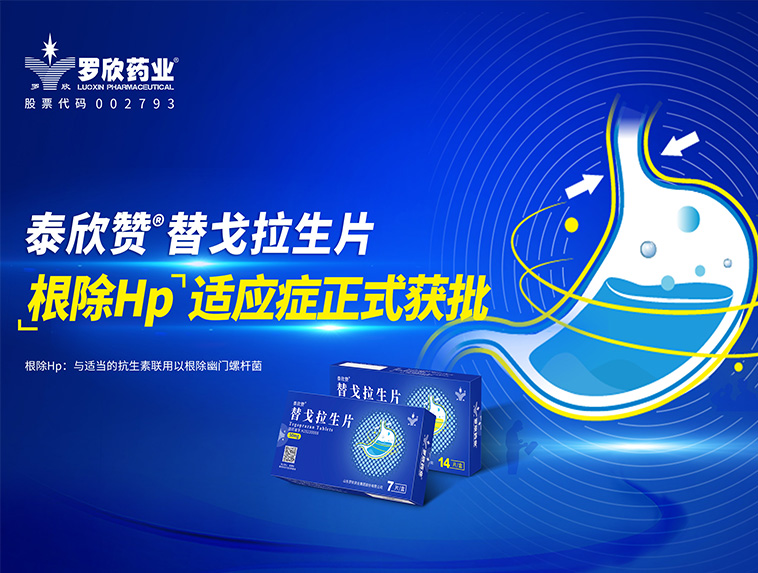

羅欣藥業創新藥替戈拉生片(商品名:泰欣贊?)新適應癥“與適當的抗生素聯用以根除幽門螺桿菌”獲批上市

國內首個獲批三項適應癥的P-CAB